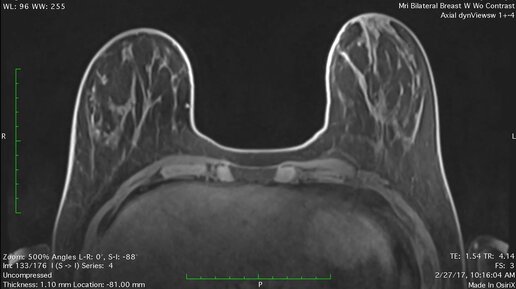

Что видно на МРТ молочных желез (видео)